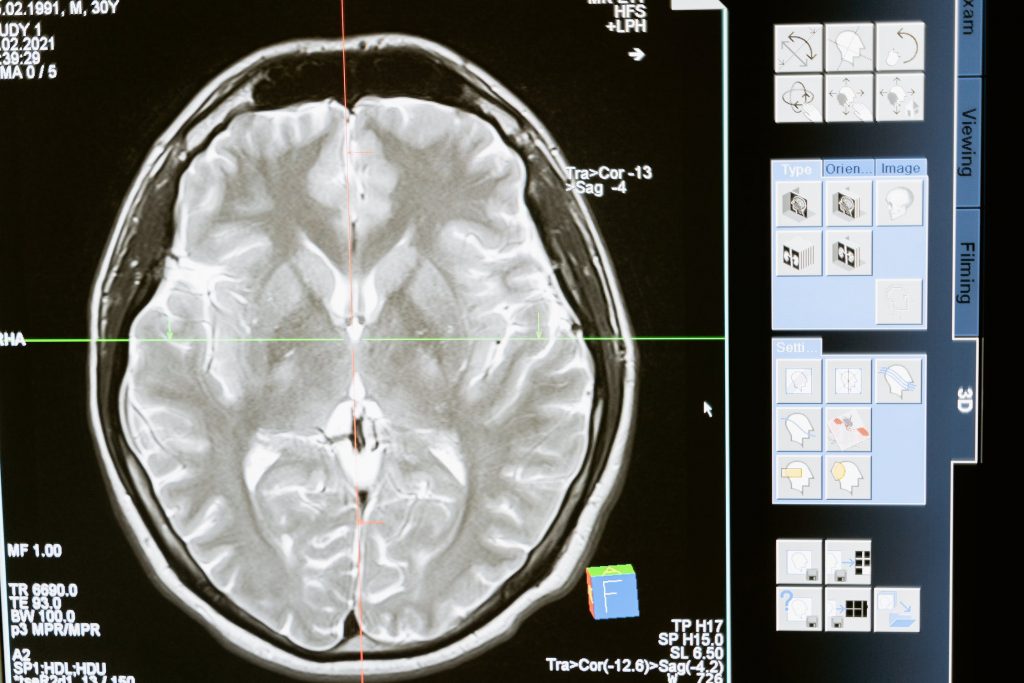

Mozog sa skladá z niekoľkých častí, z ktorých každá zodpovedá za iné funkcie

Mozog sa skladá z niekoľkých častí, ktoré majú rôzne funkcie. Napríklad, kôra prefrontálneho laloku je zodpovedná za kontrolu impulzov a rozhodovanie, zatiaľ čo hipokampus je zodpovedný za pamäť.

Mozog môže prekonať poškodenie pomocou neuroplasticity

Neuroplasticita je schopnosť mozgu sa meniť a prispôsobovať sa na základe nových skúseností. To znamená, že mozog môže prekonať určité formy poškodenia a prispôsobiť sa, aby dokázal zvládať nové úlohy.